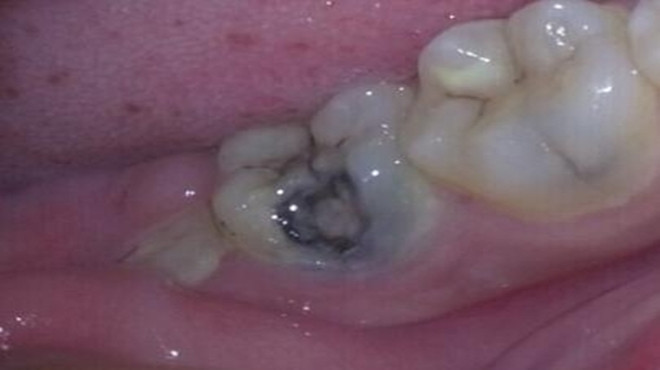

很多人因为常吃甜食或是过于刺激的食物,而没有及时刷牙,又或是晚上没有养成刷牙的好习惯,时间久了导致口腔内细菌的滋长,就可能诱发牙齿疾病。一般蛀牙就是这样生成的,牙齿表面出现黑色的小洞,若任其发展,小洞就会越来越大,吃饭塞牙,最终疼痛难忍。

蛀牙严重后会伤害到牙髓,到时候就会引发牙髓炎、根尖周炎等感染疾病,治疗起来就会更加的费事了,需要的时间与金钱也会增加很多。